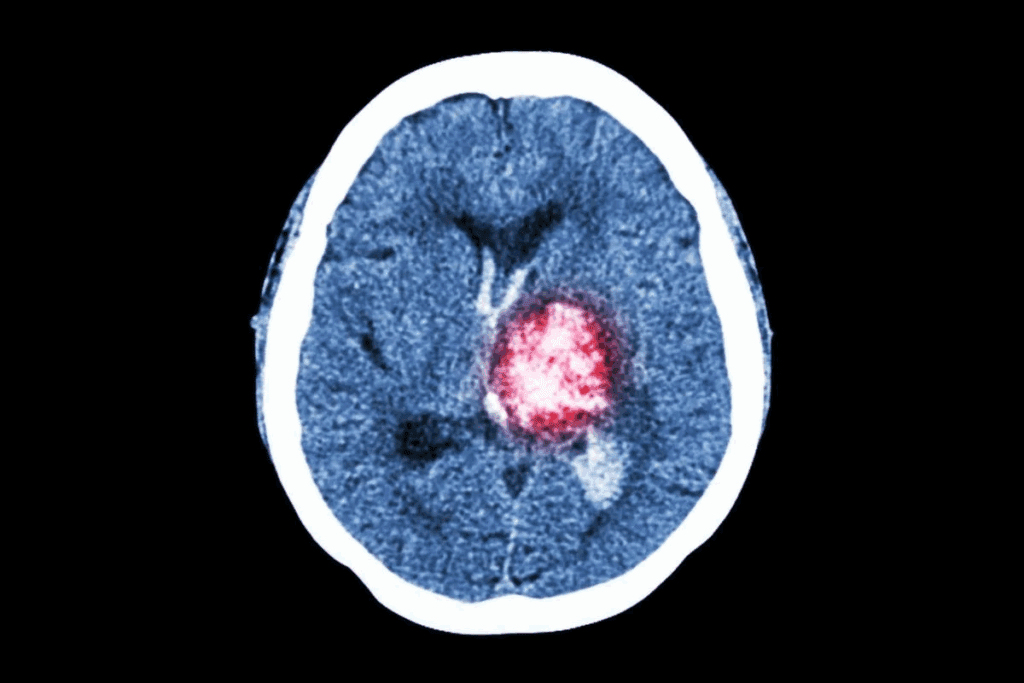

Imaging Techniques (MRI, CT Scans)

Imaging is key in finding brain tumors in kids. We use MRI and CT scans to see the tumor and where it is.

MRI gives detailed brain images without radiation. CT scans are quicker and good for emergencies.